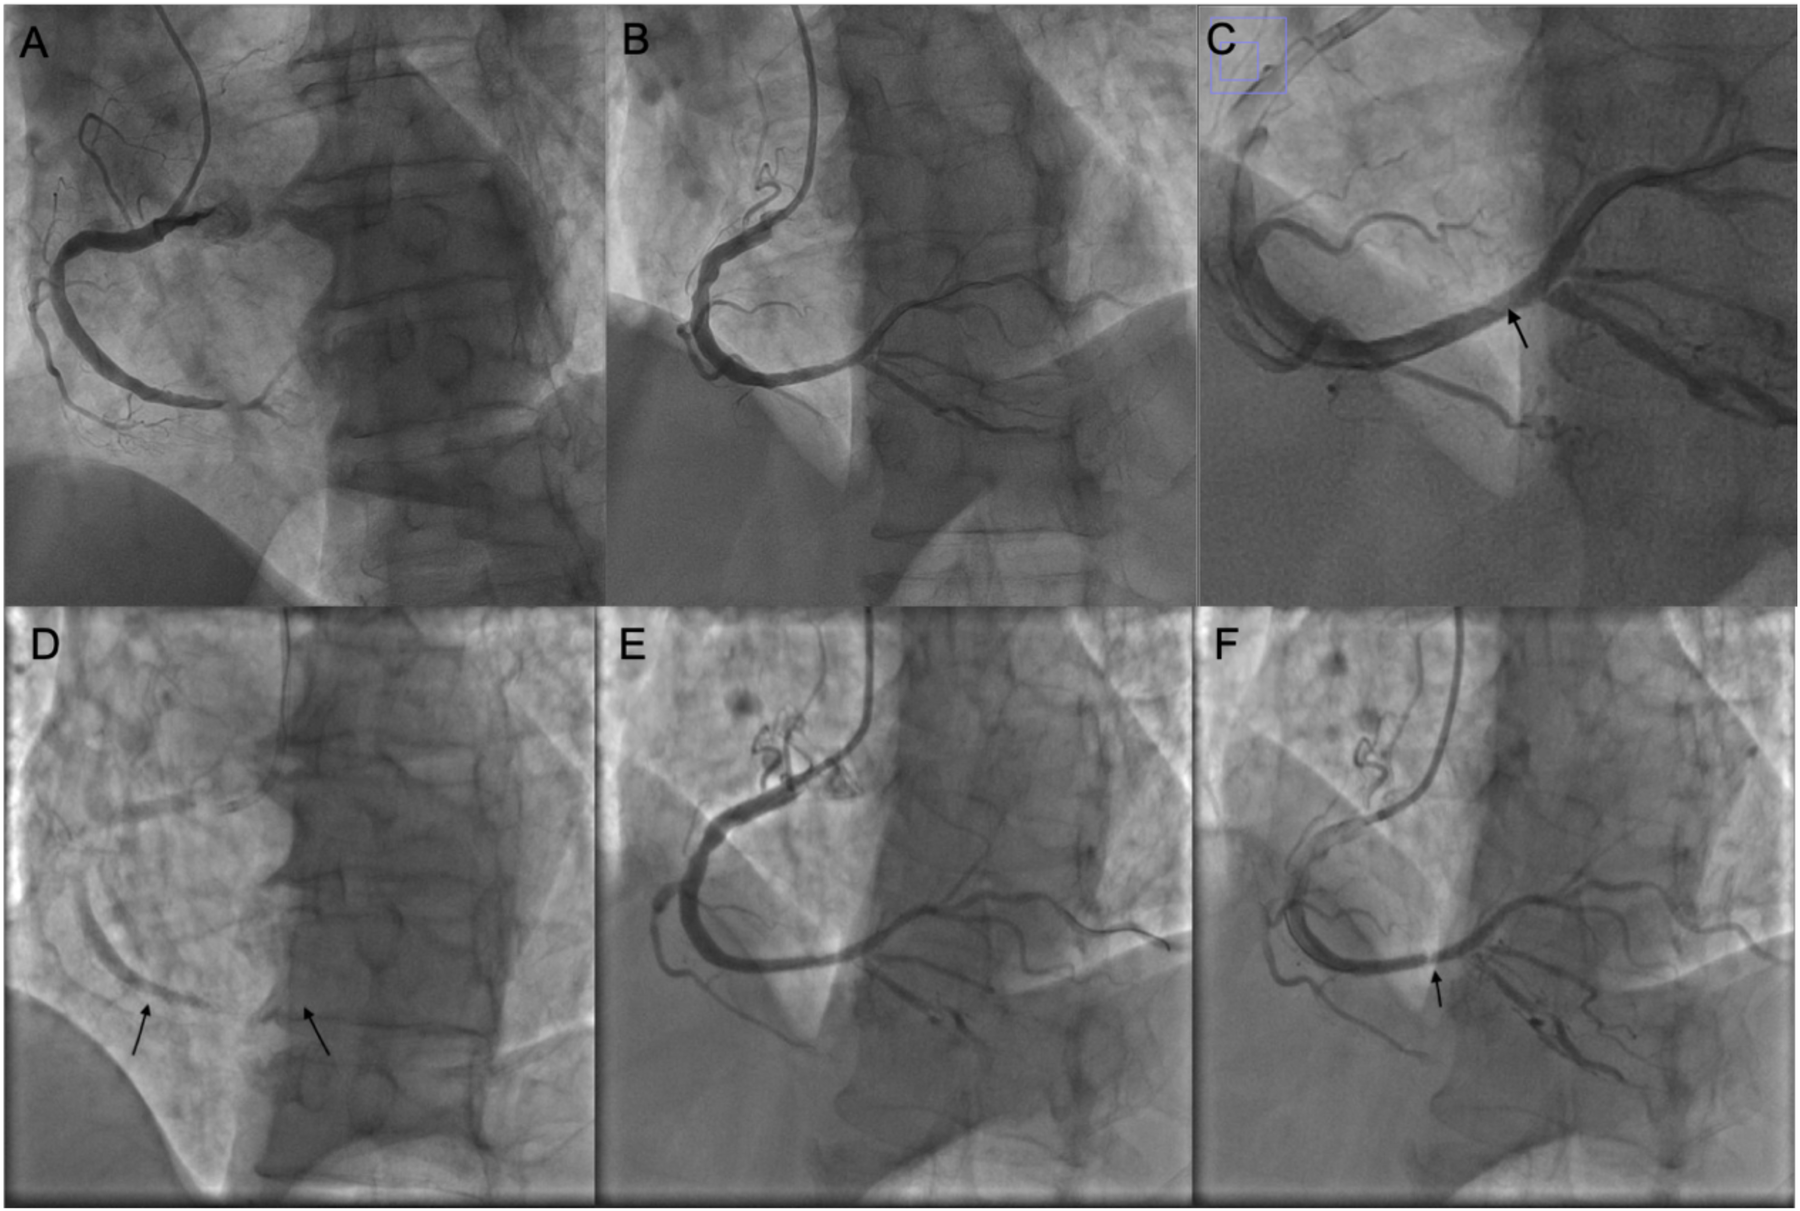

Figure 1

Coronary intervention images of the patient. (A) Coronary angiography showing subtotal occlusion of the posterolateral branch. (B) After the first PCI procedure. (C) Magnified image of panel (B); the arrow indicates a pale area within the stent. (D) Before the second PCI; arrows indicate the proximal and distal edges of the stent. (E) After balloon dilatation during the second PCI; no dissection is observed at the stent edges. (F) Before concluding the second PCI, the pale area within the stent is noted again.

No evidence of edge dissection (Figure 1).

Approximately 60 min post-op, the patient experienced recurrent chest pain. ECG again showed ST-segment elevation in inferior leads. Urgent repeat PCI was performed. Angiography revealed acute stent thrombosis with total occlusion in the RCA. Intra-procedural ACT: 290 s Balloon dilatation with 2.0 × 15 and 3.0 × 12 mm balloons restored flow. No edge dissection observed.

Repeat angiography revealed focal “hazy” appearance in mid-stent, consistent with tissue prolapse. Further balloon dilation with NC Senor 3.0 × 15 mm (14 atm, 30 s) partially improved haziness. Repeat IVUS confirmed persistent tissue prolapse.

After several minutes, angiography again showed worsening of haziness, confirming acute stent thrombosis secondary to tissue prolapse, refractory to balloon dilation.

A 3.5 × 16 mm drug-eluting stent (Boston Scientific Promus Premier) was implanted at 12 atm for 20 s.

Final angiography showed excellent stent apposition, no dissection or rupture, TIMI 3 flow.